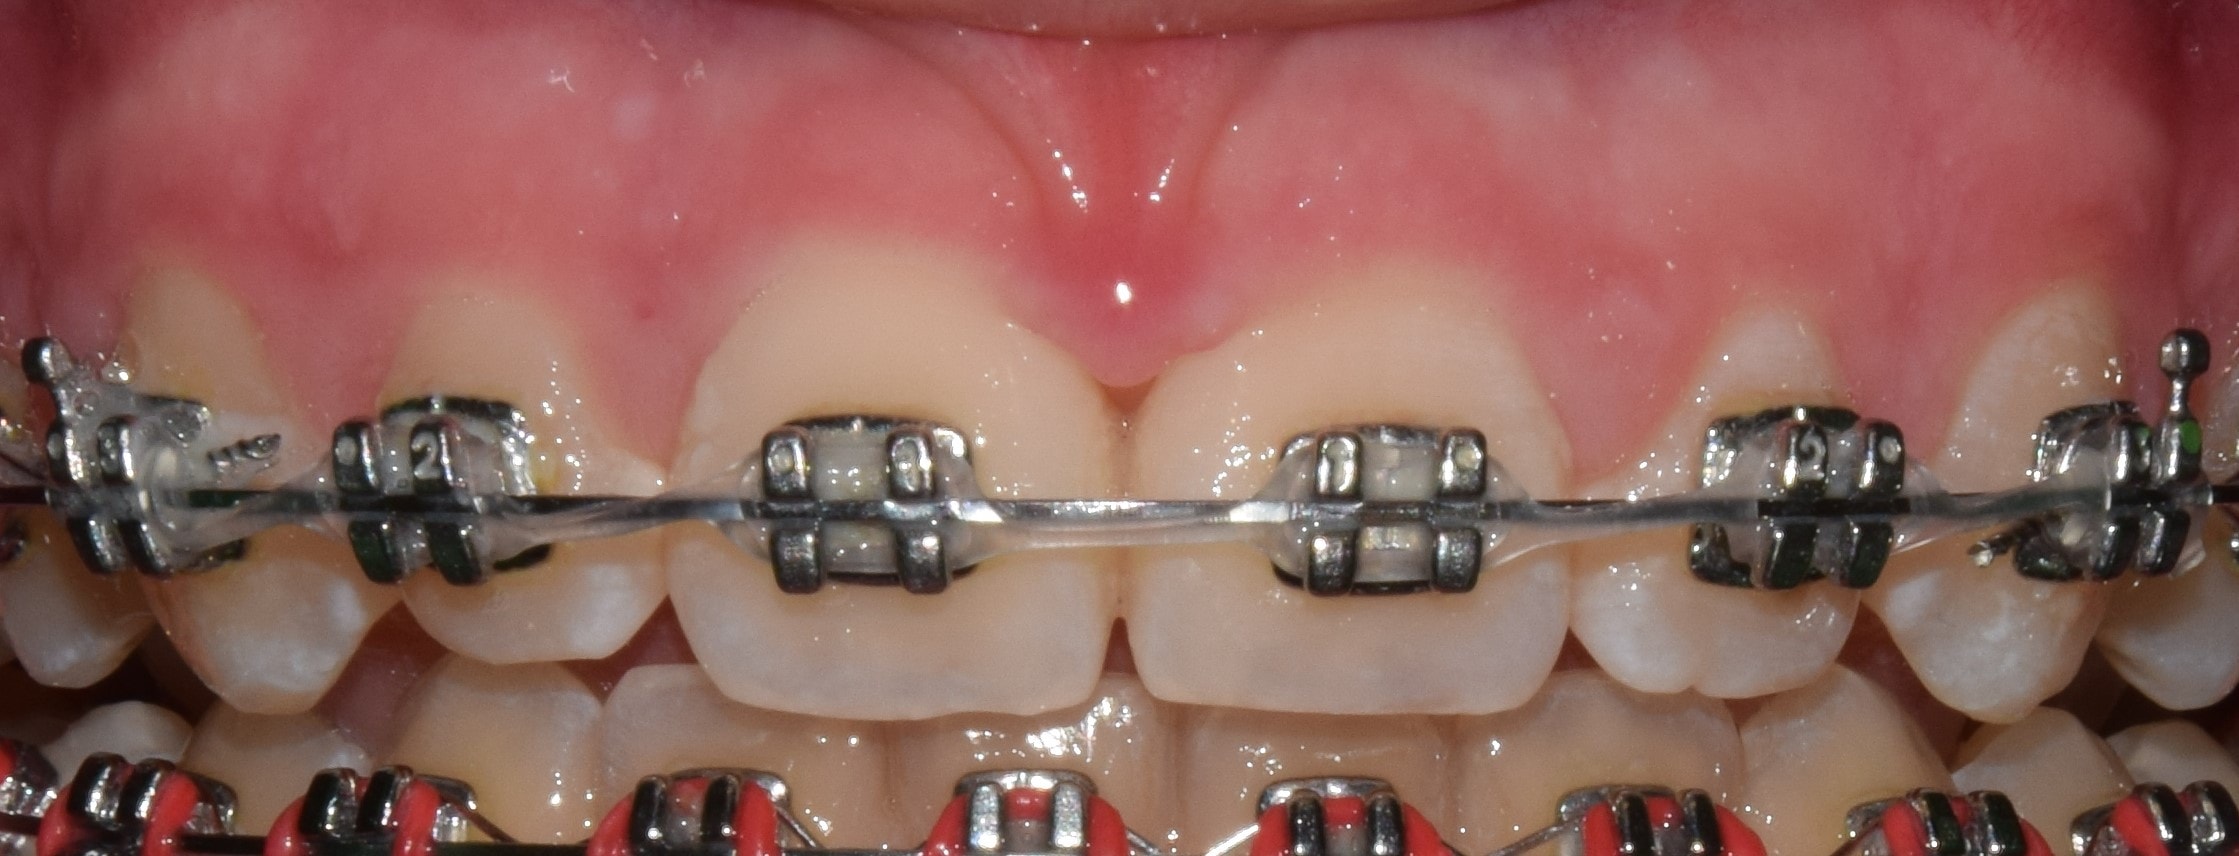

Dezorientációs sín

Általában az alsó fogív fogaira készült átlátszó sínről beszélünk, melynek rágófelszínén átlátszó akrilát van. Súlyosabb állkapocsízületi problémák kezelésénél használjuk. A sín lényege, hogy egyenletes, sima felszínt biztosít a felső fogívvel történő érintkezés során. Ezáltal kiiktatjuk a kóros fogérintkezéseket, relaxáljuk a rágóizmokat, és az ízület a számára legkényelmesebb helyzetbe kerülhet.